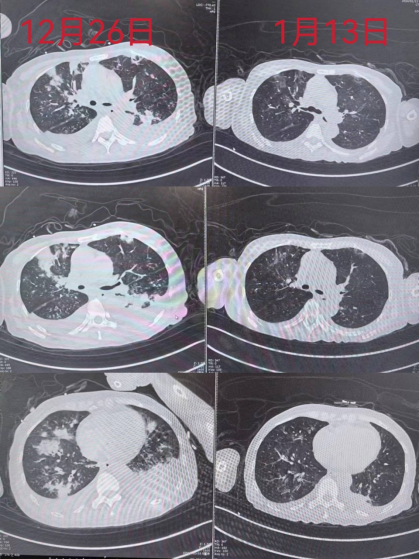

患者入院期间经历了重症肺炎,呼吸衰竭,脓毒血症,多脏器衰竭,甲乙流,血小板减少等系列疾病,经西医治疗及中医个体化辨证论治后,好转出院。